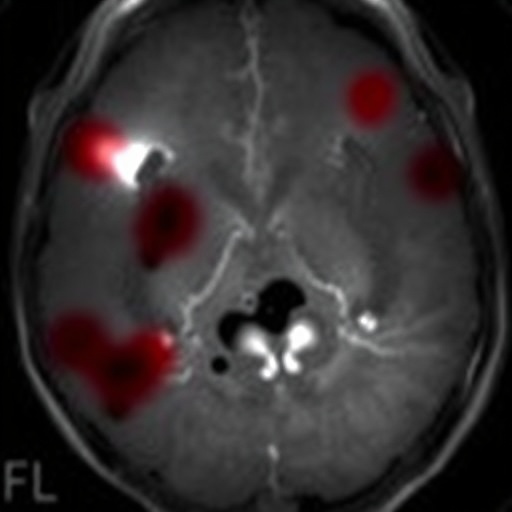

The research also highlights the importance of vigilant neuroimaging surveillance in ELBW infants to identify evolving intracranial hemorrhages rapidly. Since impaired cerebrovascular reactivity episodes often precede IVH, integrating hemodynamic monitoring data with imaging schedules might enable early detection before clinical deterioration occurs. This can facilitate prompt therapeutic intervention, potentially mitigating progression and reducing long-term sequelae.